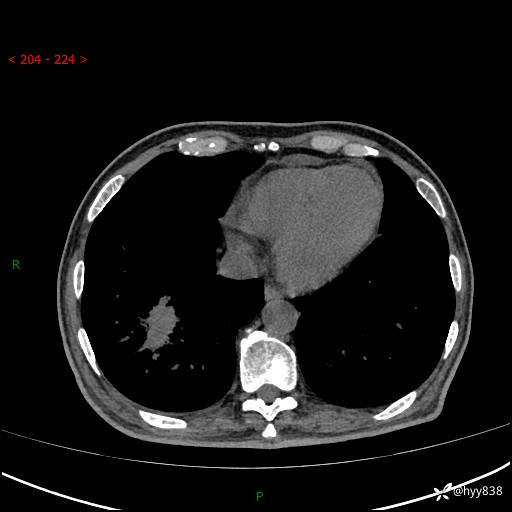

66岁/男,确诊髓系白血病5月,乏力伴气促半月。孤立结节,“晕”的厉害---结果公布~

【患者信息】:66岁/男

【主诉】:确诊髓系白血病5月余,乏力纳差伴气促半月

【现病史及既往史】:患者5月前无明显诱因出现牙龈出血,未重视,2024.5.10社区体检查血常规发现全血细胞减少,后自觉活动后心慌气促,无发热、头痛、咳嗽咳痰、胸痛等,为进一步诊治来我院,门诊以“全血细胞减少”收入,入院后完善相关辅检入院后确诊急性髓系白血病。于2024.06.11给予阿扎胞苷+维奈克拉化疗,给予输血、升白细胞、抗过敏、止血治疗,化疗后粒细胞缺乏,转入层流病房,出现发热,予以抗感染(头孢唑肟、莫西沙星、美罗培南)、抗真菌(卡泊芬净、氟康唑)、利尿、调脂、利胆、护心、护胃、调节免疫(羟氯喹、白芍总苷)、通便、调节胃肠道菌群、营养支持等对症治疗,出院时患者牙龈出血、咳嗽咳痰、腹胀、便秘等不适较前好转,复查血常规提示白细胞计数升高,要求出院,建议继续住院观察,但患者仍要求出院,予以办理。2024-08-06到我院规律化疗,2024-08-08给予阿扎胞苷+维奈克拉化疗,给予输血、升白细胞、抗过敏、止血治疗,化疗后粒细胞缺乏,转入层流病房,出现发热,予以护心、护胃 、营养支持等对症治疗,好转后出院。院外自行停用维纳克拉。半月前患者无明显诱因出现乏力、纳差、活动后气促,无心慌、胸闷,无咳嗽、咳痰,无畏寒、发热等不适,现患者为求进一步诊治来我院,门诊以“急性髓系白血病”收入院。 发病以来,患者精神、饮食欠佳,睡眠一般,大小便如常,体力明显下降,体重无明显减轻。

【检查】:胸部CT平扫